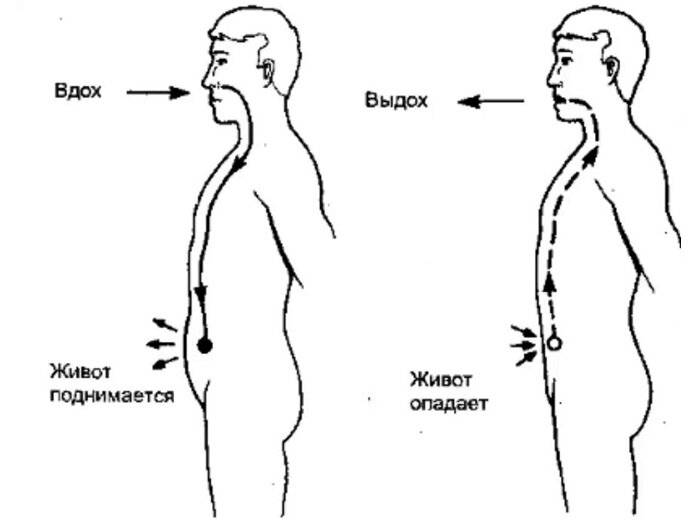

- Закройте рот и медленно вдохните через нос, чувствуя, как живот поднимается и надувается, как воздушный шар.

Самый эффективный способ дышать — это “опускать воздух вниз, к животу”. Когда диафрагма опускается вниз, живот расширяется, чтобы наполнить легкие воздухом.

“Дыхание животом” эффективно, поскольку тянет легкие вниз, создавая отрицательное давление внутри грудной клетки. Это приводит к поступлению воздуха в легкие.

- Второй способ зависит от опущения грудобрюшной преграды по направлению книзу. Это – диафрагма, имеющая куполообразную форму. Грудные мышцы отвечают в процессе дыхания за то, чтобы этот купол тянулся вниз, освобождая простор для легких. Середина опускается книзу и создается нужный объем. Из-за опущения грудная часть диафрагмы давит на живот, в результате выпячивается его стенка.

- Диафрагмальное (брюшное), когда в момент вдоха живот выступает вперёд, а на выдохе подтягивается по направлению к позвоночнику.

Главный орган в брюшном дыхании — диафрагма. Диафрагмальная мышца — это куполообразная перегородка, она отделяет грудную клетку от органов, расположенных ниже в брюшной полости. На вдохе диафрагмальная мышца идёт вниз и сжимается, заставляя брюшную стенку выдвигаться вперёд. В момент выдоха диафрагмальная мышца возвращается вверх и приобретает форму купола, выгоняя воздух из лёгких.